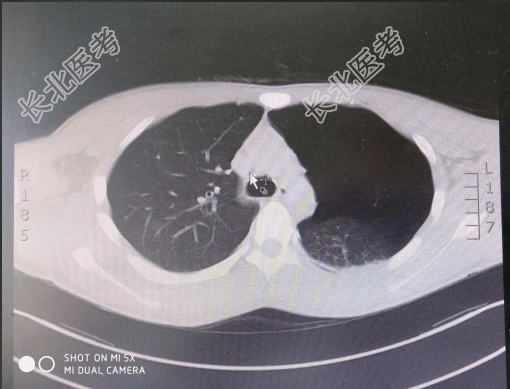

- [材料题] 【一般资料】男性,19岁,学生【主诉】剧烈运动后出现左侧胸痛,伴胸闷1天【现病史】患者1天前,跳远后后出现胸痛,呼吸时明显,休息后无缓解,伴有胸闷,无咳嗽、咳痰,无发热,无放射性疼痛,无咯血、晕厥,2018-10-20门诊行肺CT检查阅片提示:左侧气胸,为求进一步诊治,门诊拟“气胸”收入我科,病程中患者神清,精神可,饮食一般,睡眠一般,大小便正常,体重未测。【既往史】一般健康状况良好;否认高血压病史。否认糖尿病病史。否认冠心病病史。否认慢性支气管炎病史。否认胆结石病史。否认胆囊炎病史。否认“肝炎、伤寒”等传染病病史。未发现药物、食物过敏史。无手术史。否认输血史。【查体】T:36.3℃,P:75次/分,R:20次/分,BP:118/75/mmHg。神清,精神可,步入病房,自动体位,言语清晰,查体合作。皮肤黏膜:无黄染皮疹,无瘀点、瘀斑,无紫绀水肿。浅表淋巴结未触及肿大。头部无畸形,双瞳孔等大等圆3mm,对光反射存在;外耳道无脓性分泌物,听力正常;鼻畅,鼻腔无脓性分泌物;咽无充血,扁桃体不大,伸舌居中。颈软,气管居中,甲状腺不大,颈静脉无怒张,肝颈反流征(-)。左侧胸廓呼吸运动减弱,触觉语颤减弱,叩诊呈鼓音,听诊左侧呼吸音减低,未闻及明显干湿啰音;心率76次/分,律齐,各瓣膜听诊区未闻及明显病理性杂音。腹平软,肝脾肋下未及,无压痛反跳痛,移动性浊音(-),肠鸣音正常。脊柱四肢生理弯曲存在,活动自如,双下肢无水肿。肛门外生殖器:未检。生理反射存在,病理反射未引出。【辅助检查】胸部CT提示:左侧气胸。